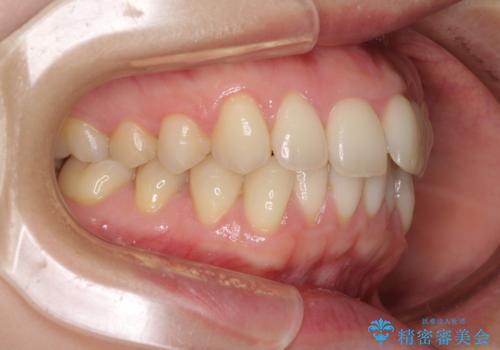

- 上下の前歯のデコボコを気にして来院された患者様です。

妊娠中であり、途中通院が難しくなる可能性があることから、インビザラインによる矯正治療を行うこととしました。

上下顎歯列全体の後方移動とIPR(歯と歯の間を削る)によってデコボコが解消するように設計しました。